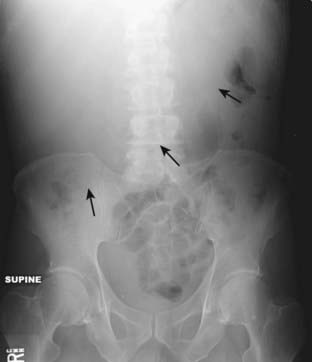

Figure 13-1 Normal supine abdomen.

This is the “scout” film of the abdomen, the one that gives a general idea of the bowel gas pattern and allows you to search for radiopaque calculi and detect organomegaly. There is usually a small amount of air in about two to three loops of nondilated small bowel (solid black arrow). There will almost always be air in the stomach (dotted black arrow) and in the rectosigmoid (solid white arrow). Depending on the amount of fat around the visceral organs, their outlines may be partially visible on conventional radiographs. The psoas muscles are outlined by fat (dotted white arrows) making them visible on this image.